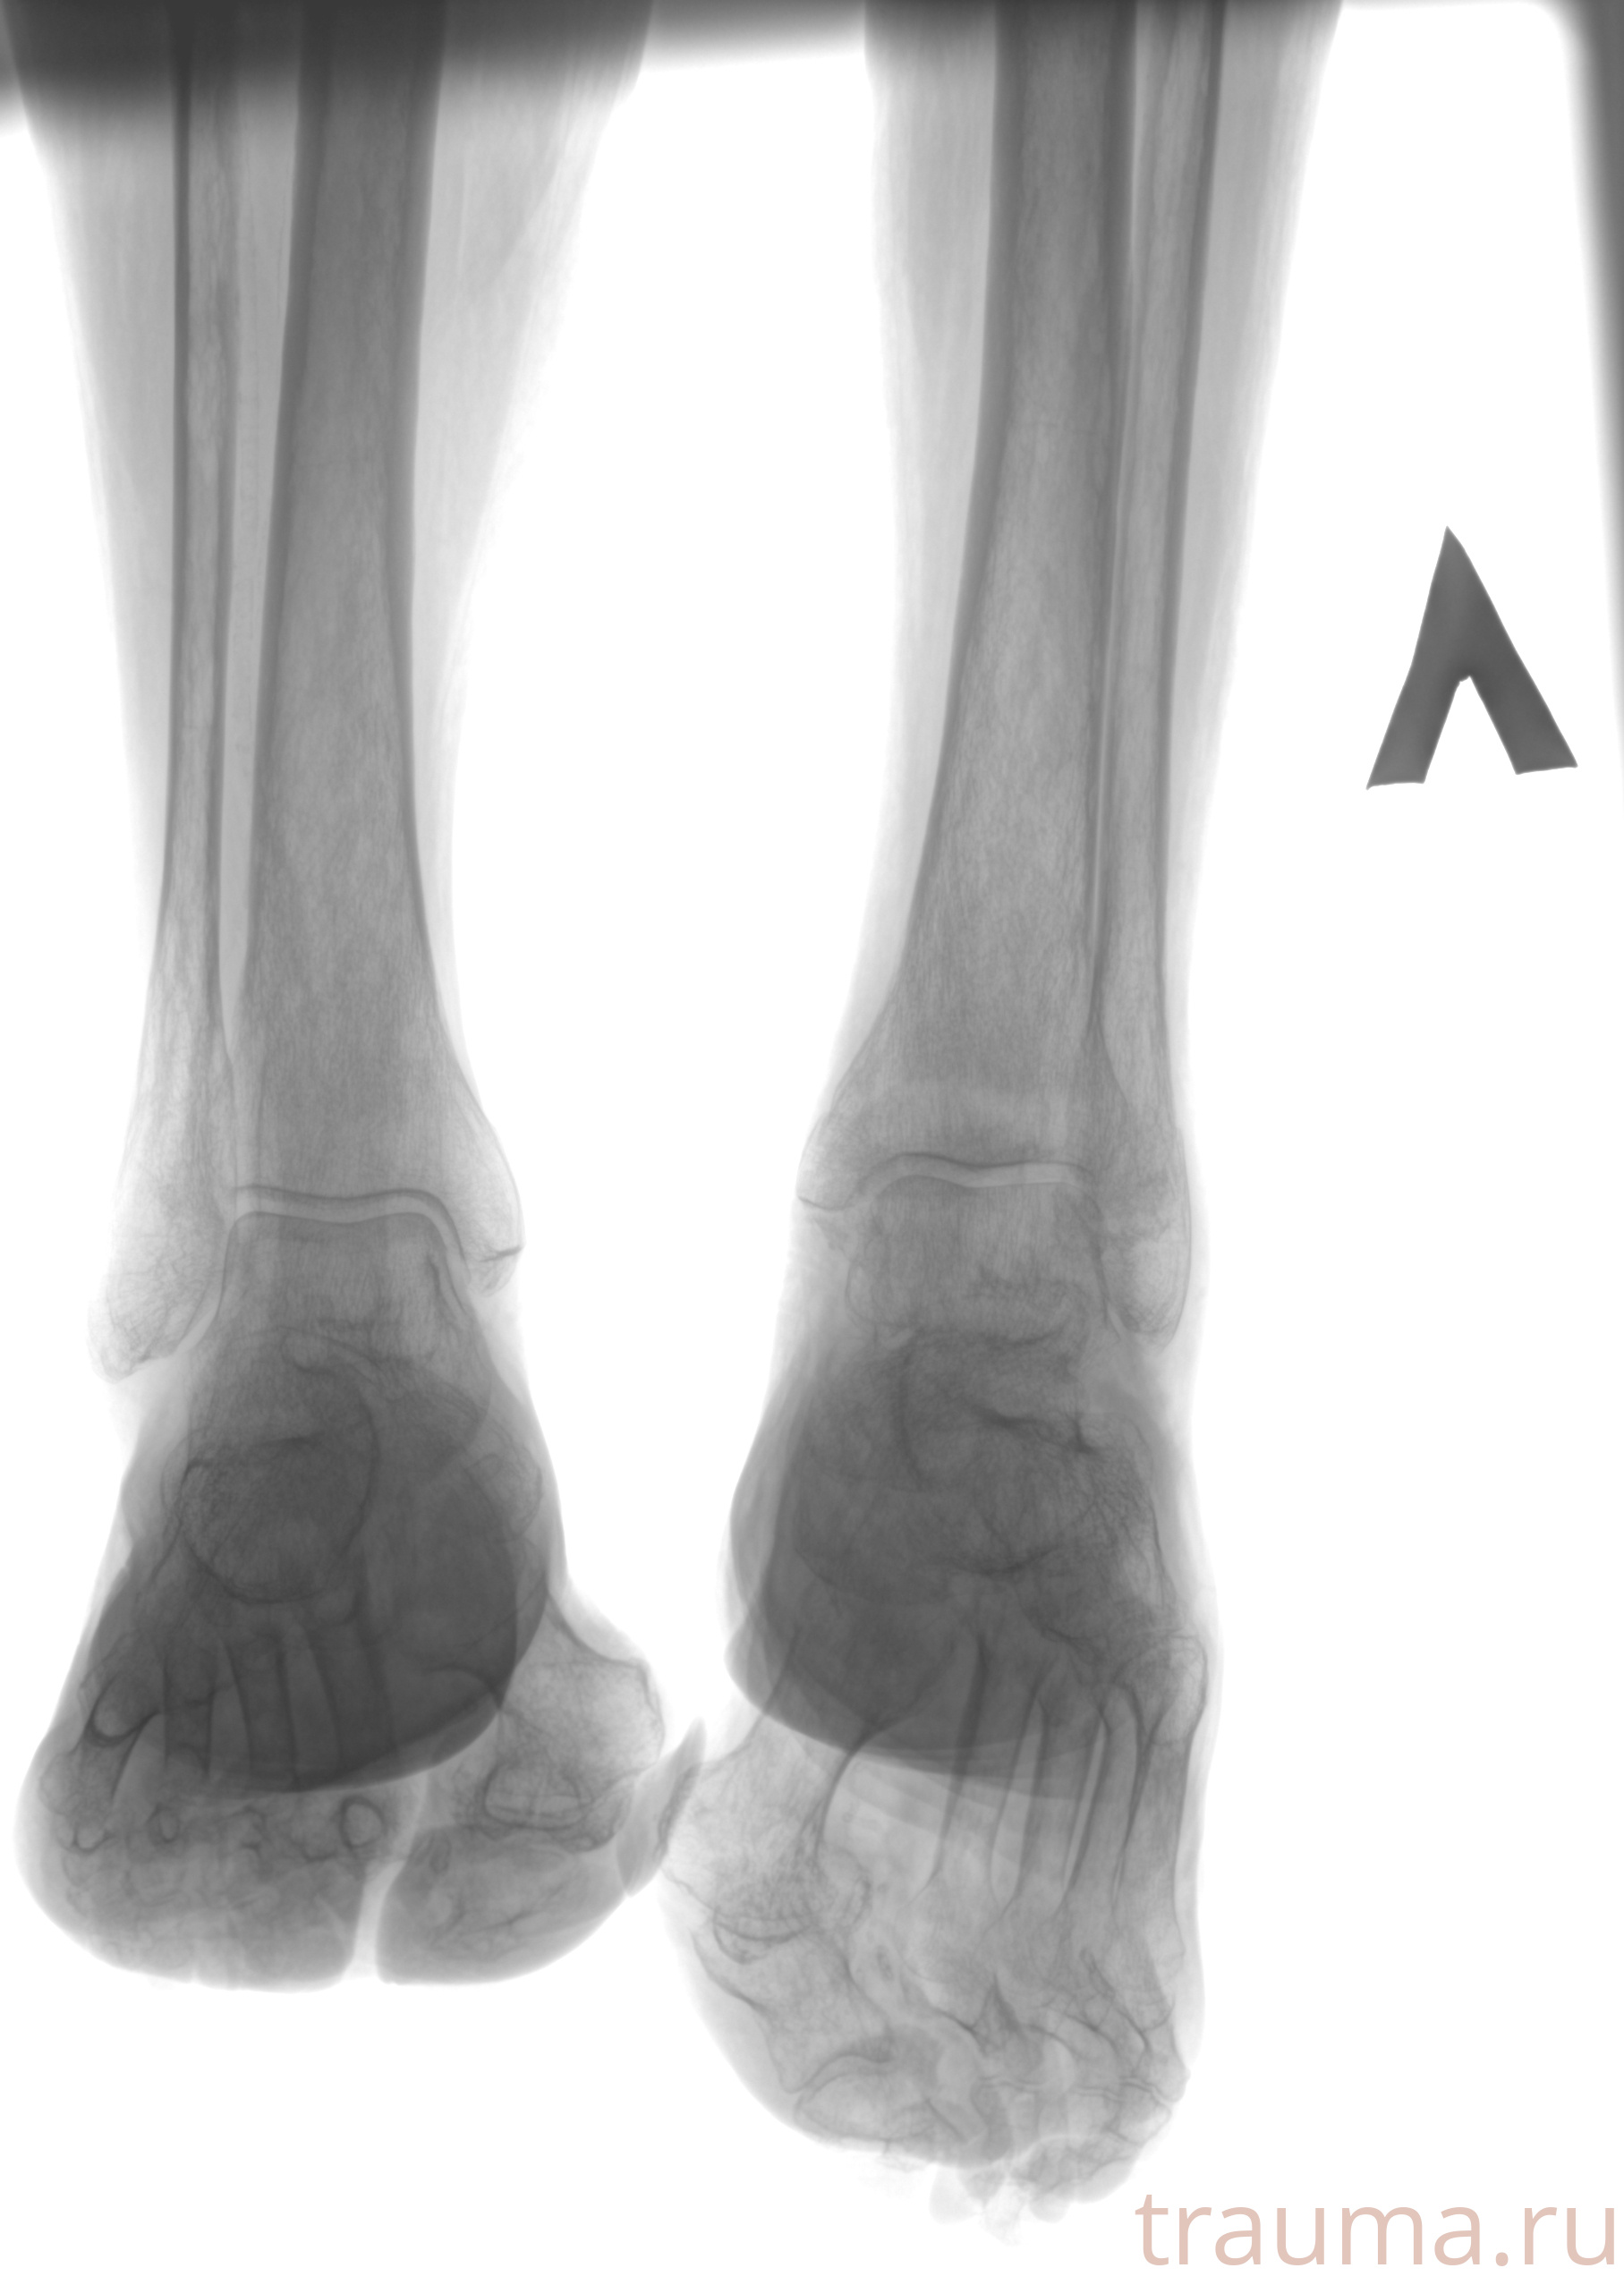

Рентгенограммы

Рентген на дому: по вашему адресу приезжает врач-рентгенолог, травматолог-ортопед с мобильным рентгеновским аппаратом, проводит диагностику травмы или заболевания, делает необходимые рентгенограммы, дает рекомендации по дальнейшему лечению. Получить качественные снимки в домашних условиях возможно благодаря уникальной методике, разработанной МосРентген Центром для института  Склифосовского